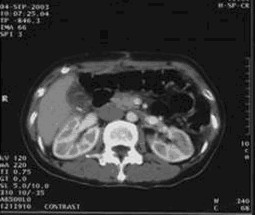

女,49岁。胃体癌晚期,胃窦增厚强化,与周围粘连,腹膜增厚,腹腔广泛转移,伴大量腹水。放/化疗失败,无法手术。治疗方案:腹腔灌注今又生2×1012VP/2次/周,共12周,同时灌注顺铂和5-氟尿嘧啶腹腔,后4周加8次全腹热疗。治疗后:第3周,腹水消失;第8周,胃窦、腹膜和网膜变薄,盆腔结节明显变小。后行手术切除残余胃肿瘤,术中探查全腹和盆腔未扪及肿瘤。术后病检胃肿瘤内未见癌细胞。

治疗结束:第12周,胃壁回复正常